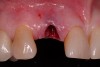

A 54-year-old, non-smoking woman presented with a root fracture at the maxillary right lateral incisor (Figure 1). The patient presented with a 10-mm pocket at the mid-facial probing depth, and a Grade 2 mobility. The preoperative peri-apical digital radiograph can be seen in Figure 2. A natural diastema existed on the distal aspect of the right maxillary incisor, and the patient did not wish to have this corrected. To hold the natural tissue emergence profiles throughout the treatment phase, the immediate implant placement and provisionalization procedure was chosen to treat the affected site. Before the procedure, an occlusal index and registration was taken so that when the retrofitting of the natural tooth shell was accomplished, the exact location of the natural tooth shell could be seated on the implant abutment at the time of implant placement (Figure 3). After administration of an appropriate local anesthetic, tooth No. 7 was removed by an atraumatic technique to preserve the natural soft tissue emergence profiles present pre-surgically (Figure 4). After tooth removal, debridement of the extraction socket was accomplished by curettage of the socket, followed by rotary instrumentation with a course #8 round diamond to ensure removal of all remnants of the periodontal ligament, granulation tissue, and localized debris. To aid in the debridement, the patient was started on a preoperative administration of Augmentin 875 mg, taken the day before treatment, and once again 1 hour before the surgical visit. The patient then continued this antibiotic course for a total of 10 days.

Figure 3  Indexing the exact position of the natural tooth shell.

Figure 3